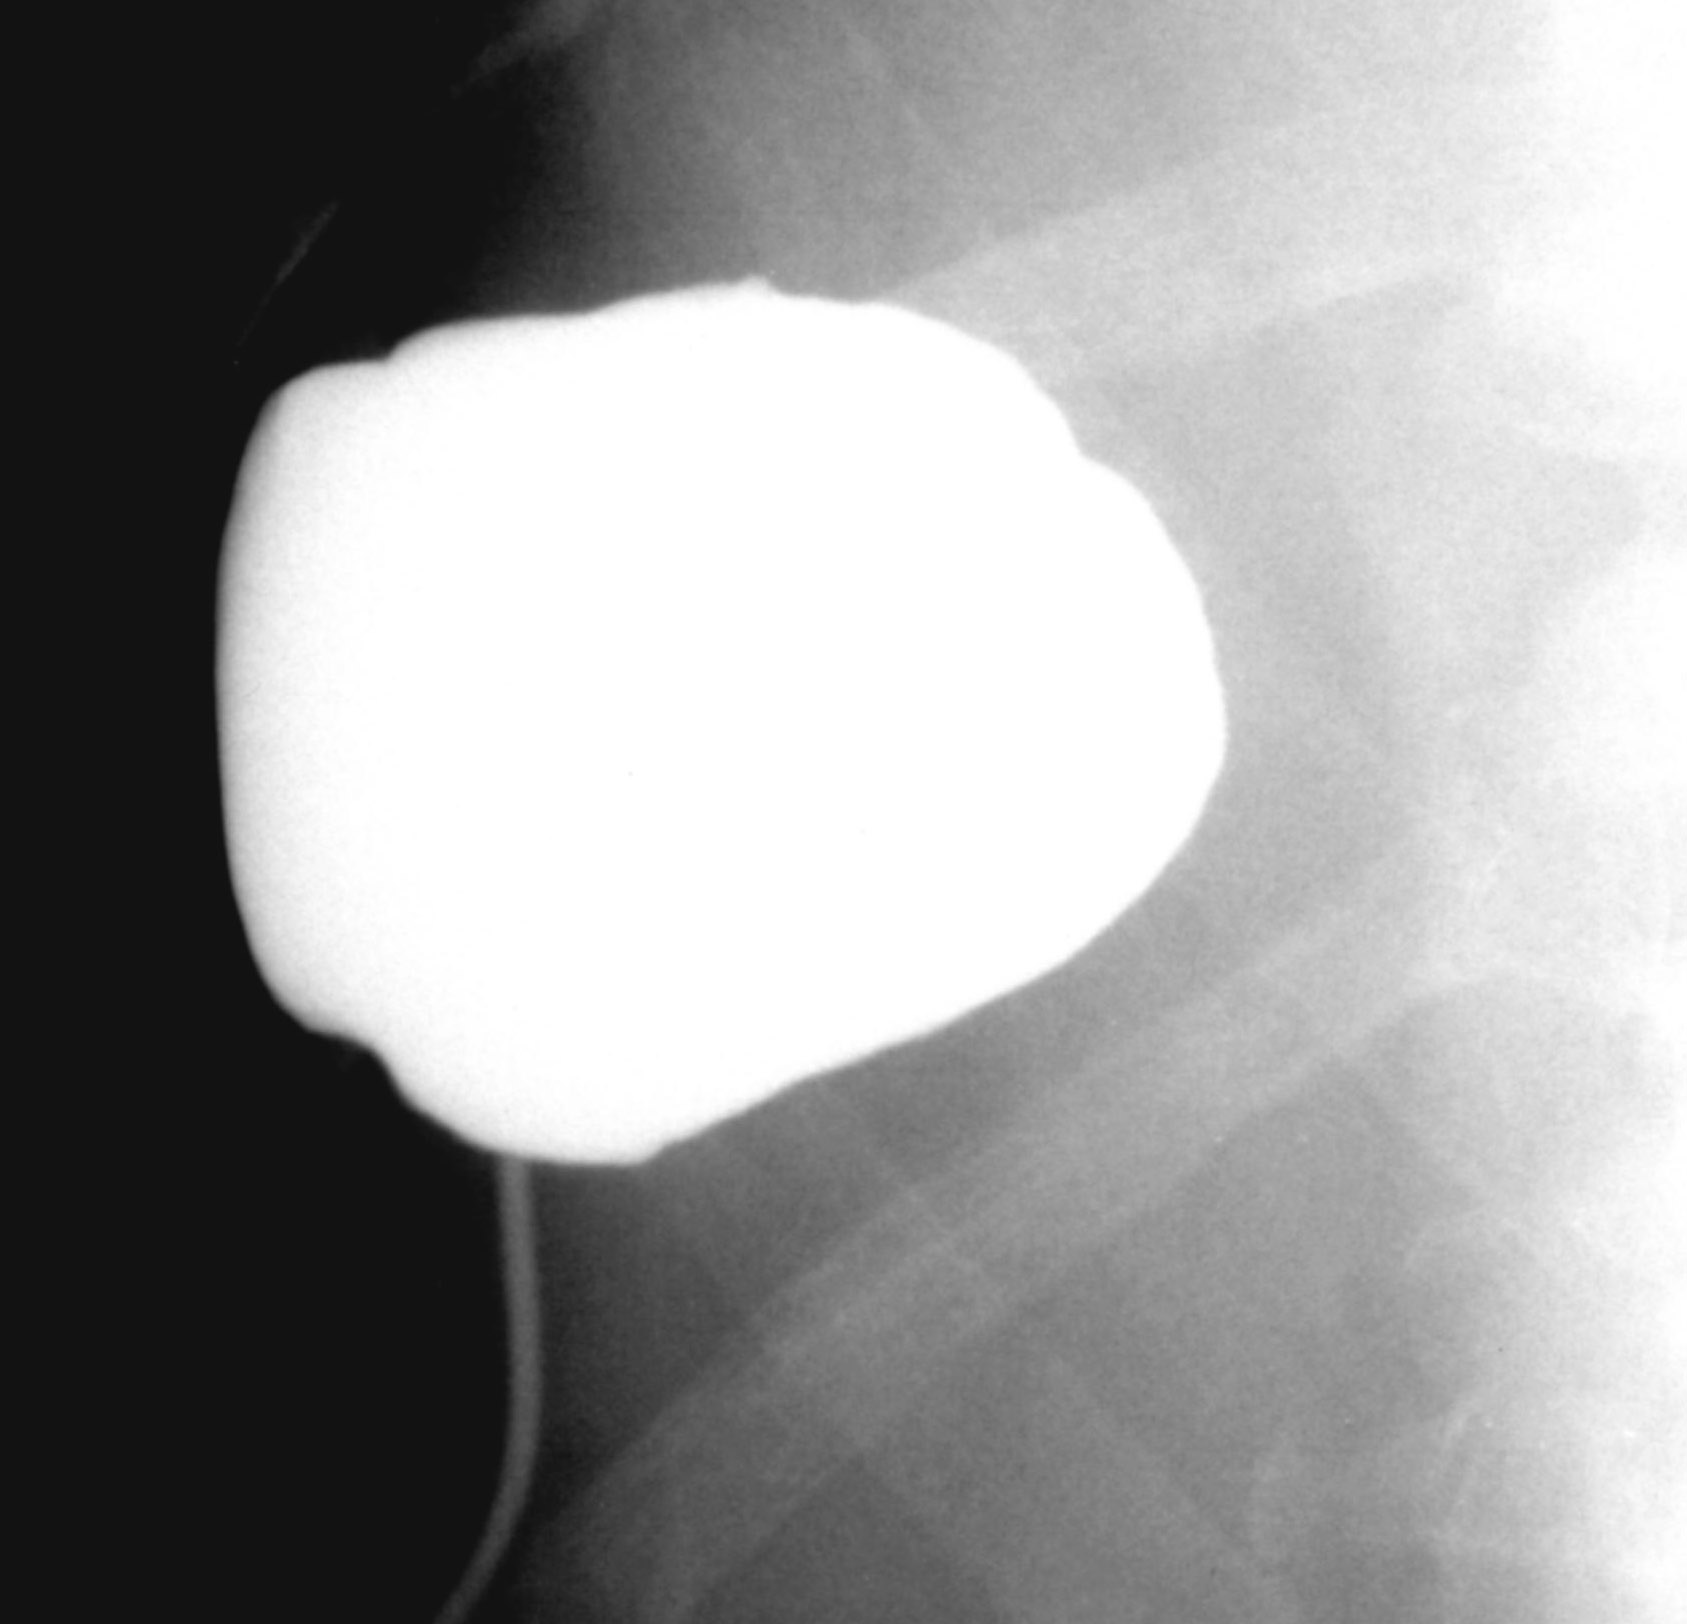

Compared to the surgical methods of past, nowadays these cystic lesions can be successfully treated percutaneously with alcoholic cyst sclerotization. (Figures 26., 27.).

Image

Figure 26. – Percutaneous ethanol cyst sclerotization ( filling up of the cyst before the sclerotization)

A

B

Figure 27. – US and CT examinations before percutaneous ethanol sclerotization (A: US examination, B: CT examination)

The puncture of the cyst is usually guided with US (rarely with CT). The puncturing needs to take place from the parenchymal side of the cyst. When its contents are removed the empty cavity is filled up with diluted contrast material to ensure that there is no contrast leakage to the surroundings. The 96% ethanol is only injected after the contrast material has been removed and no leakage was found. (The volume of the alcohol should not exceed 50-60% of the cyst or 100 ml.)

The injected ethanol is left in the cyst for 20 minutes. Following this, the alcohol is drained as well. Cystic regression is then regularly controlled with US or CT examinations. (Figures 28., 29.) Patient complaints usually cease within 4-6 weeks after the treatment.